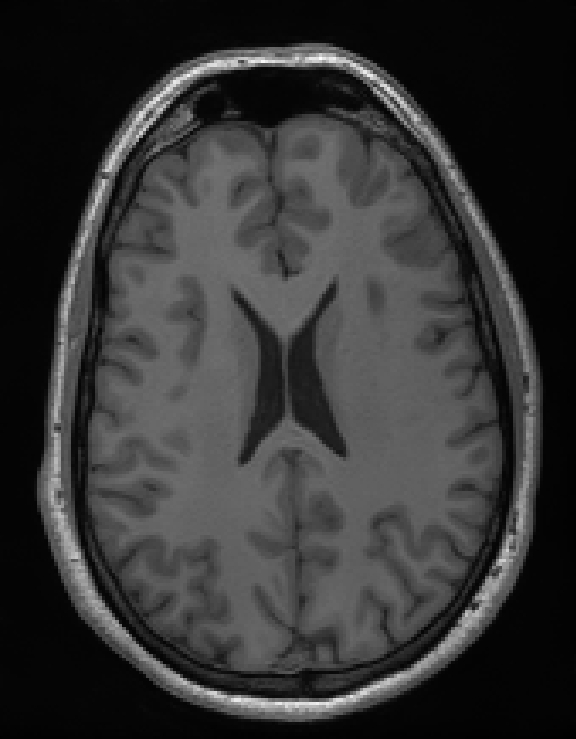

Illustrations of the normal operator approximation on the Walnut-CBCT dataset. (top row) Original volume slice $\vx$, exact normal operator evaluation $\mA^\top \mA \vx$, and approximated normal operator $\mH\vx$. (bottom row) Learned filter $\bm{\lambda}$, learned mask $\vm$, and squared approximation error $(\mA^\top \mA \vx - \mH \vx)^2$.

Illustration of our reconstruction method on real 3D cone-beam data. On the left, axial slice with [30/1200] views, and on the right, vertical slice with [30/1200] views. Our method significantly reduces the streaking artifacts and noise compared to the standard FDK reconstruction, while preserving fine details.